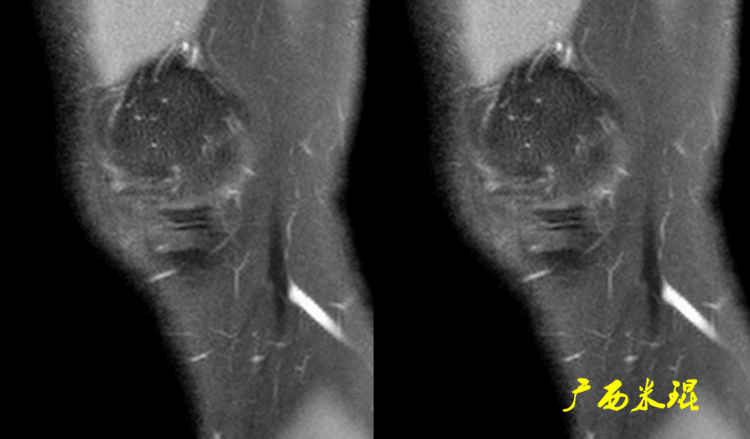

下面这张MR矢状位显示为类似双后交叉征,后交叉韧带前下方的低信号其实是正常的外侧半月板后角,半月板桶柄状撕裂多发生于内侧,绝大多数是前交叉韧带损伤的合并伤,此病人的前交叉韧带正常,通过其他截面的半月板阅片就能排除。